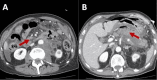

Ischemic colitis is thought to be an injury to the colon as a result of reduced blood flow. Certain infectious diseases such as the Epstein-Barr virus can aid in the reduction of blood flow. The insult can range from inflammation and superficial injury to full-thickness necrosis. The typical regions affected are the "watershed" areas of the colon: the splenic flexure, the rectosigmoid junction, and the right colon. Because patients can present with a wide spectrum of symptoms from vague abdominal discomfort to complete abdominal catastrophe, the diagnosis of ischemic colitis is sometimes challenging to make. Patients typically present with the acute onset of crampy abdominal pain and usually pass blood mixed with stool within 24 hours. Endoscopically, ischemia is suspected in the presence of bluish hemorrhagic nodules from submucosal bleeding, cyanotic or necrotic mucosa with bleeding ulcerations, or a segmental distribution with an abrupt transition point between injured and normal mucosa. We present a case of an 80-year-old male with a history of hypertension, hyperlipidemia, and basal cell carcinoma of the scalp diagnosed with ischemic colitis associated with positive Epstein-Barr virus B cell lymphoma.